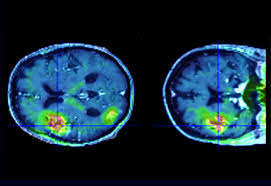

Avc Accident Vasculaire Cerebral Causes Symptomes Traitemnts Sante Magazine

visitez l'article complet ici : https://www.santemagazine.fr/sante/fiche-maladie/avc-accident-vasculaire-cerebral-177349

C'est quoi un accident vasculaire cérébral ? L'institut national des désordres neurologiques et des avc note qu'une personne recevant un cela peut très bien être un signe d'avc et, dans tous les cas, c'est le signe que quelque chose ne va pas. Les signes de l'avc chez la femme.

Problème de vue (la femme victime d'avc peut voir double, avoir une vue qui baisse ou tout simplement ne plus voir d'un côté). Ce détail est important pour les traitements à venir ; L'avc peut laisser d'importantes séquelles sur les personnes qui en ont souffert ou entraîner la mort dans bien des cas.